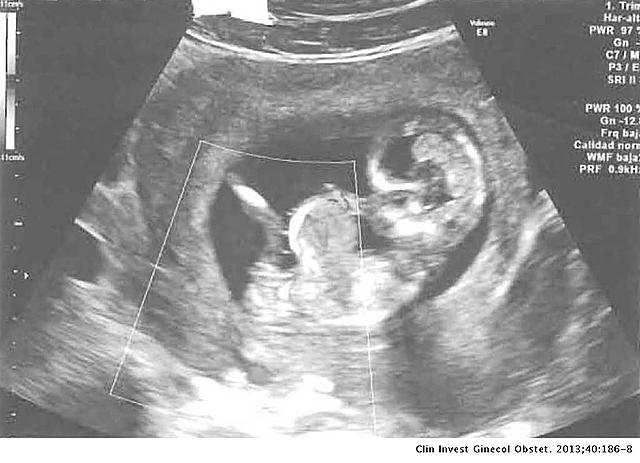

Embrion

DESARROLLO EMBRIONARIO